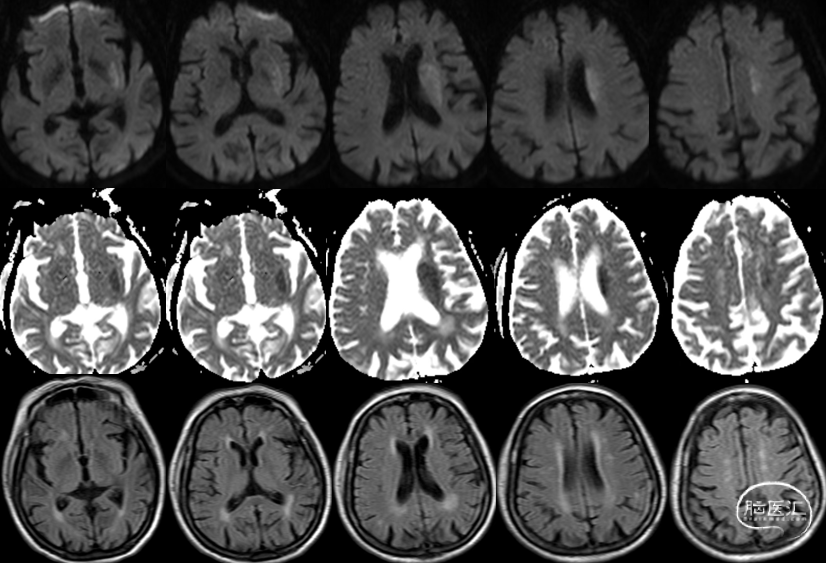

术前MRI

术前MRA:左侧大脑中动脉闭塞。